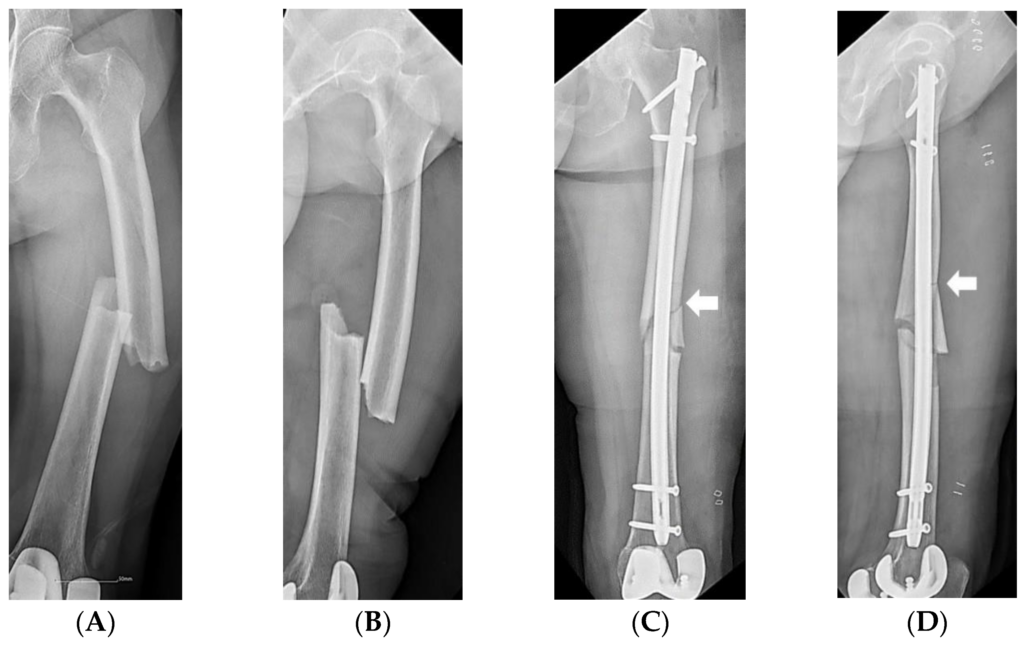

- Treatments: reduction/realignment of fracture ends, casts, pins, wires, plates, sarcoplasty, bone grafts, intramedullary nail, electrical stimulation, ultrasound stimulation

Realignment of fracture ends Intramedullary Pin

Intramedullary Pin - Possible Complications affecting Bone Fracture Healing

- Intramedullary Pin © Joo, Y.B.; Jeon, Y.S.; Lee, W.Y.; Chung, H.J. is licensed under a CC BY (Attribution) license